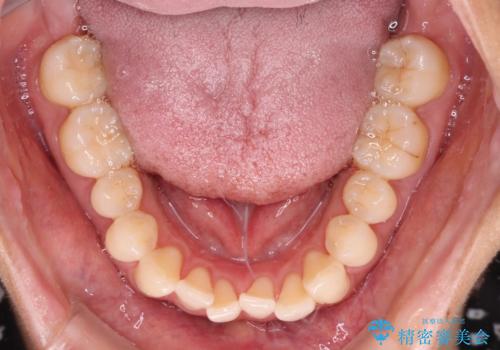

上顎前歯が捻れて前方に飛び出しており、下顎前歯もそれに沿うようにデコボコとなっていました。

IPR(歯と歯の間を削る処置)によりスペースを獲得して上下顎前歯のデコボコを改善し、飛び出している前歯が引っ込むように設定し、インビザラインにて矯正治療を行うこととしました。